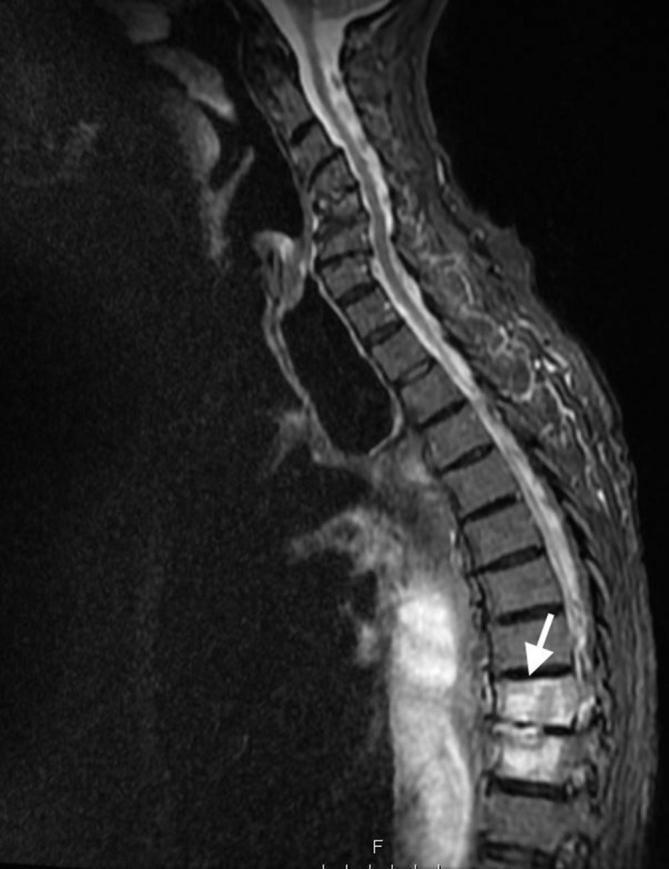

We report the case of an 84-year-old male, who presented with septicaemia, abdominal and back pain. The patient had a background of oesophageal carcinoma and had undergone previous oesophagectomy and gastric pull-up operation 10 years ago. A computerised topography scan demonstrated a probable gastro-vertebral communication with a destructive process at the T8/T9 vertebral level. Further evaluation with MRI clearly showed the tract between the two structures and confirmed the diagnosis of spondylodiscitis at the adjacent spinal level. The patient was resuscitated, treated with intravenous antibiotics and kept nil by mouth. A subsequent gastroscopy demonstrated an eroding gastric ulcer at the enteric opening of the tract between the tubal stomach and the spinal column. The diagnosis was discussed with the patient, his family and the surgical multidisciplinary team. Given the extent of disease and his multiple medical co-morbidities, the decision was made for conservative management and symptom control. This is the first case of a gastro-vertebral communication causing spondylodiscitis to be described in the literature.